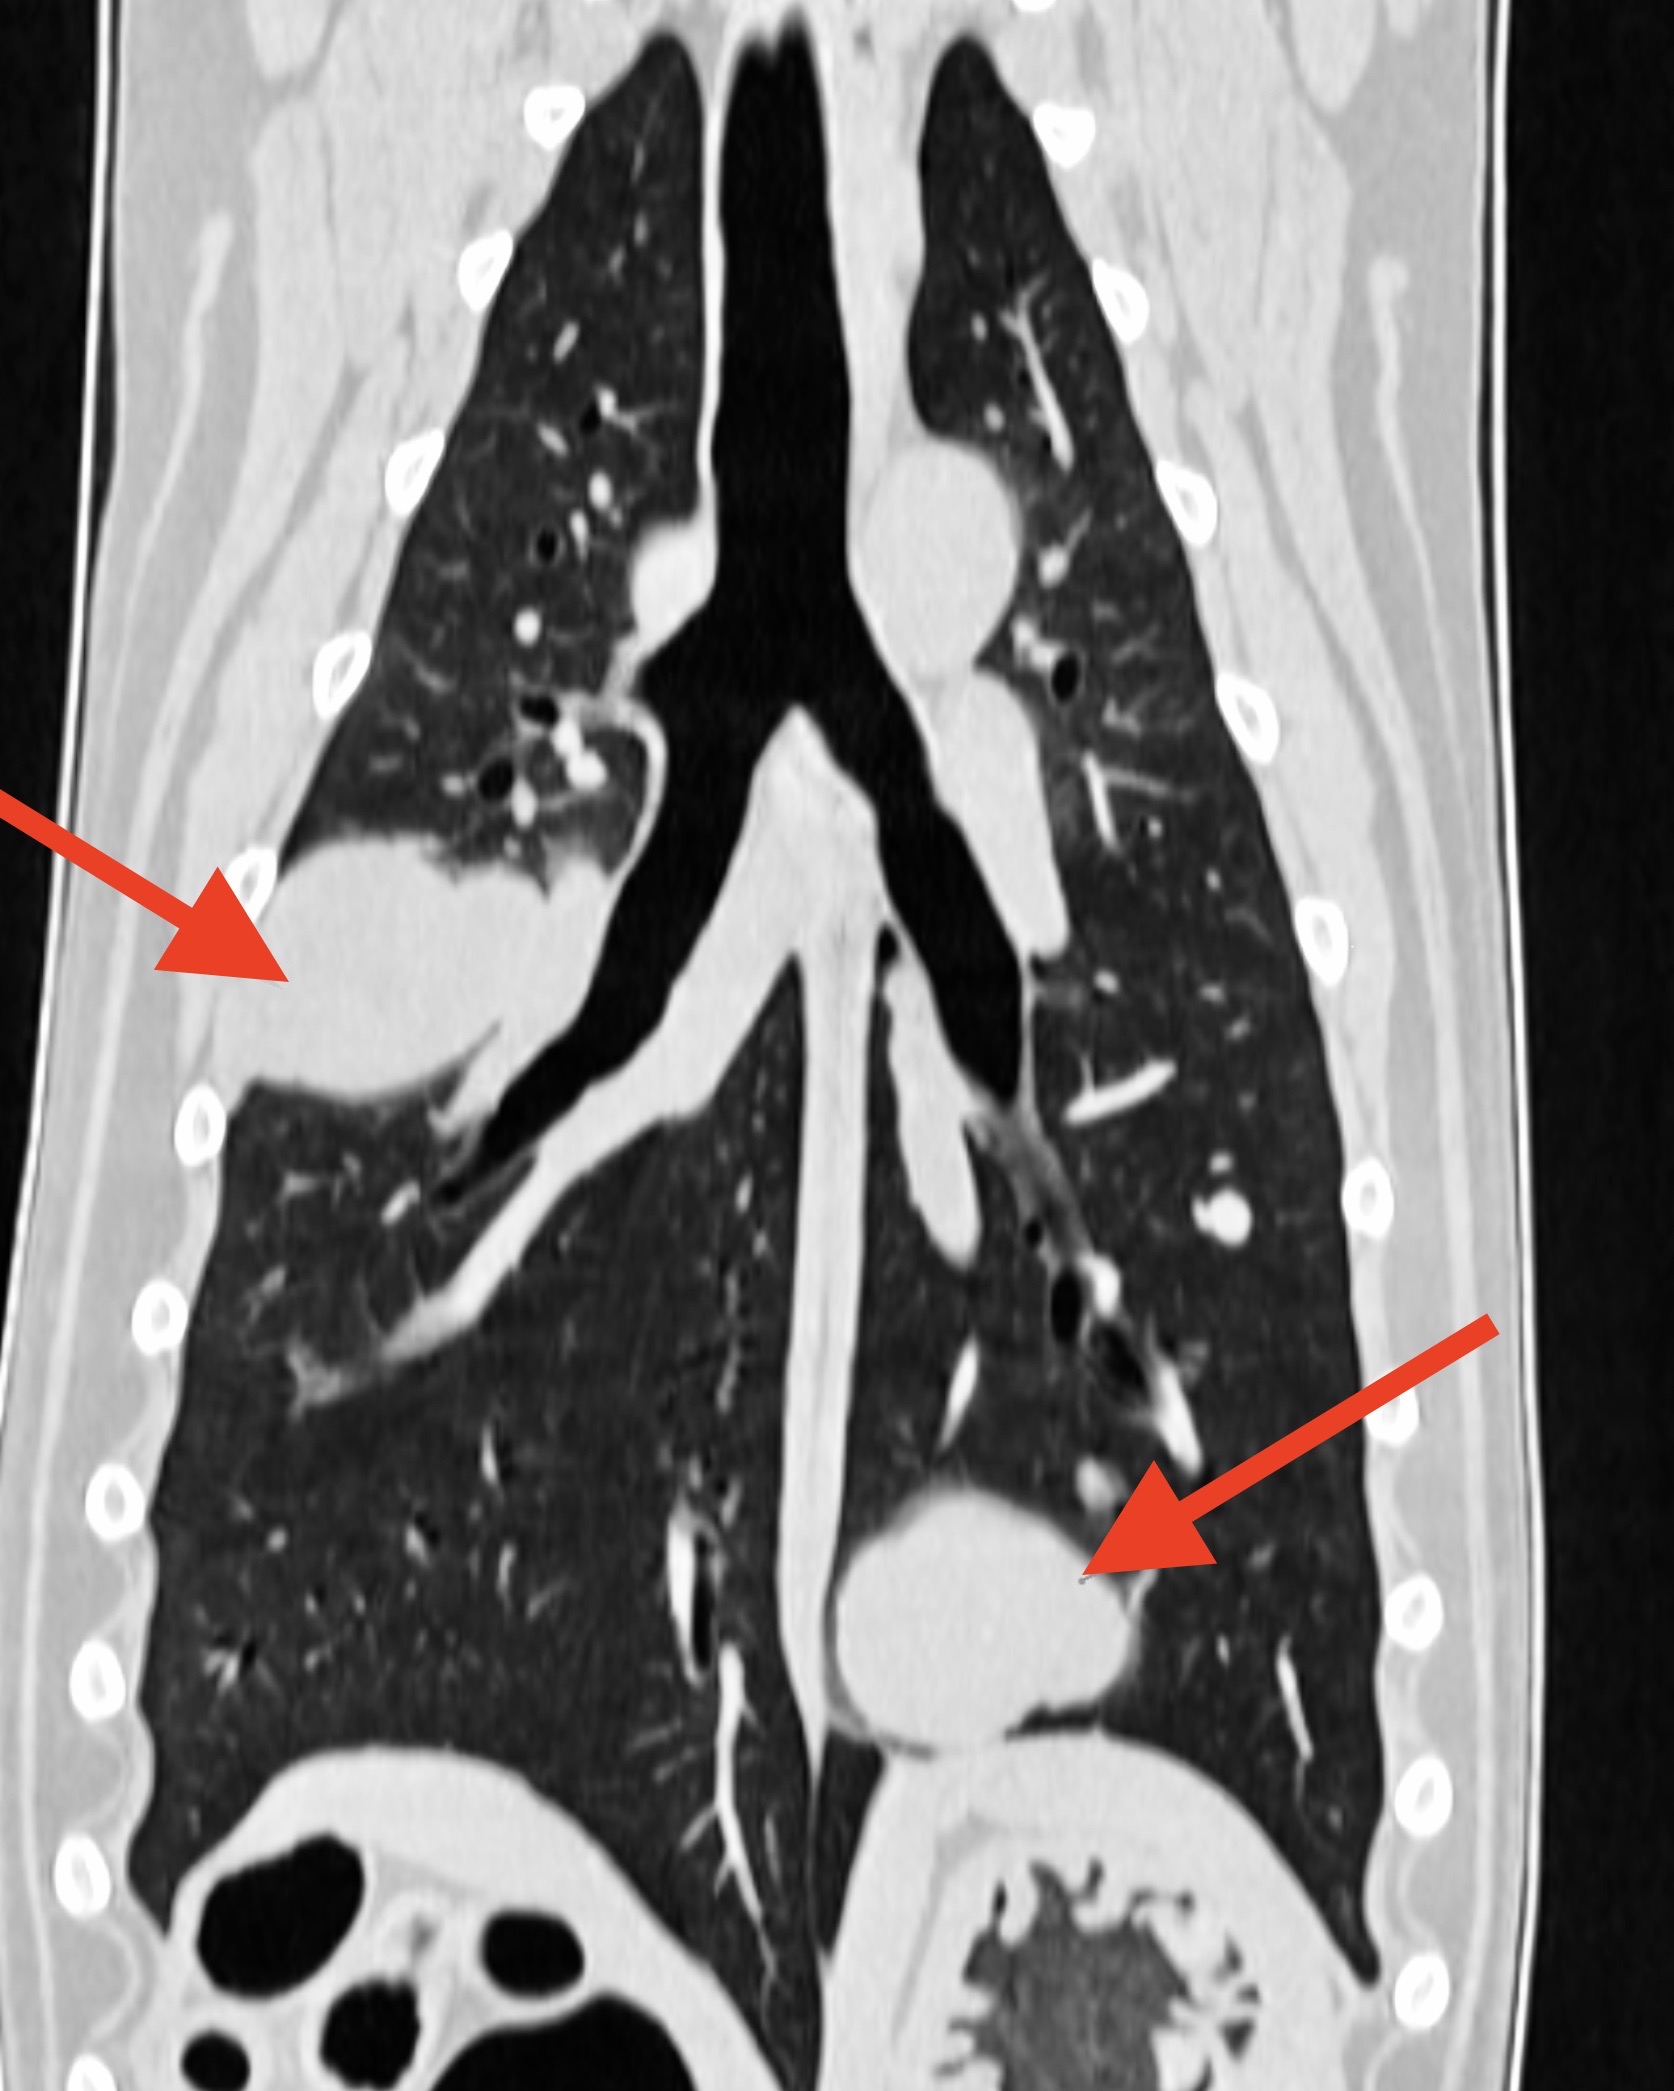

Scanner pulmonaire chez deux chiennes : à gauche, consolidation de la partie ventrale des lobes pulmonaires moyen droit et accessoire, compatible avec une pneumonie par fausse déglutition, chez une border collie atteinte de paralysie laryngée. A droite : Deux métastases pulmonaires chez une chienne présentant un carcinome mammaire de grade 3 (autrement dit, une tumeur mammaire très méchante).